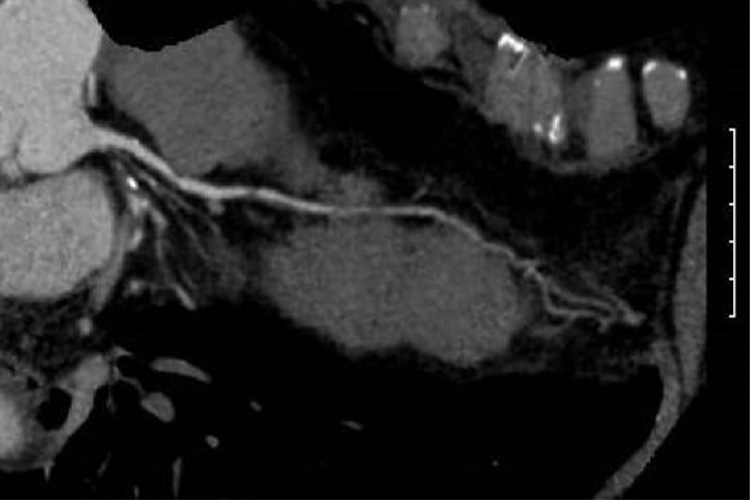

⑦冠動脈CT検査

造影剤を静脈注射し、心電図と同期させながらCTをとることで、冠動脈狭窄の有無を診断します。短時間で心臓の断面を撮影し、三次元画像で表わすことが可能です。但し脈の速い方や不整脈のある方、冠動脈石灰化が強い方では評価が難しい場合もあります。